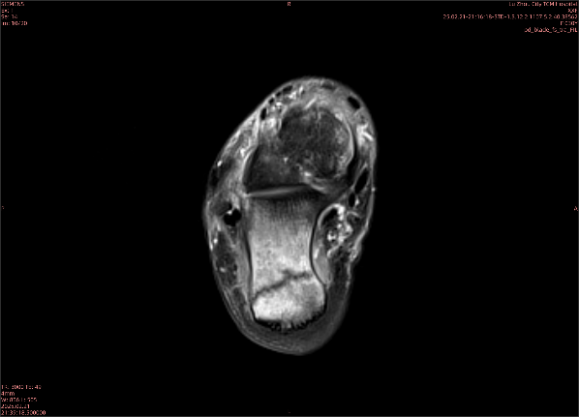

隱性骨折在MRI表現(xiàn)為T1WI序列上見由關(guān)節(jié)面向骨干走行的形態(tài)各異低信號區(qū),有線狀、條狀、紊亂低信號,信號強(qiáng)度不均勻。與T1WI低信號改變相對應(yīng)部位在T2WI上表現(xiàn)為相應(yīng)形狀的高、低混雜信號,且部分低信號周圍可見高信號水腫改變。STIR序列圖像上病灶呈顯著高信號,與信號被抑制的臨近正常骨髓形成鮮明對比,分界也較T2WI成像更為清楚。脂肪組織抑制技術(shù)是MRI的一個重要性能,脂肪抑制技術(shù)在MRI應(yīng)用中可以改善組織對比和增加病變顯示機(jī)會,這樣骨髓的脂肪抑制后就不會有任何信號,而隱性骨折線及骨髓水腫的異常高信號就會更加明顯的顯示出來。

舉例圖像

圖1

專業(yè)解釋看不懂沒關(guān)系,大家看圖1和圖2就可以了,這是同一個患者跟骨的磁共振和CT圖像,圖1的紅色箭頭指示的黑線就是磁共振圖像顯示的骨折線,一目了然。而對比圖2的CT圖像上并未顯示異常。

這下大家明白了吧,如果懷疑隱匿性骨折優(yōu)先選擇磁共振檢查